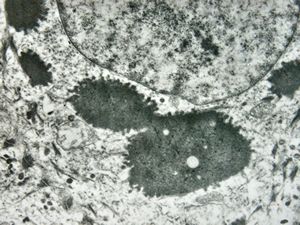

M, 43y. | myeloid leukemia … Auer bodies